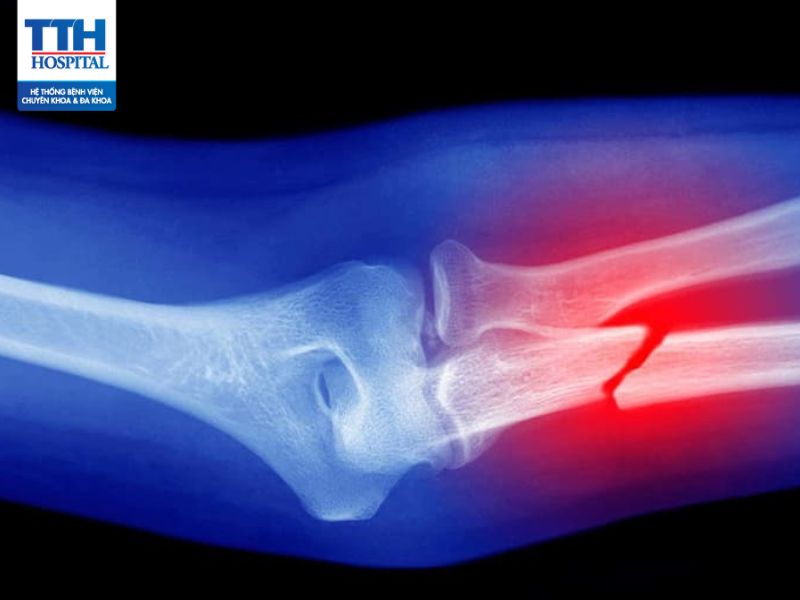

Gãy xương là tình trạng chấn thương nghiêm trọng và cần được chăm sóc đúng cách, xử lý kịp thời.

Chấn thương chỉnh hình